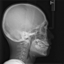

レントゲン

お顔のレントゲンを撮影すつことにより、より客感的に、例えば上顎前突(いわゆる出っ歯の状態)の原因等を診断できます。また成長期の患者さんの場合は手首のレントゲン(手根骨といいます)を撮影し、現在骨格の成長のどのステージにいるのかを正確に診断します。